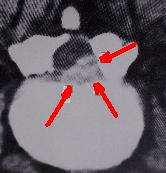

Before the advent of CT scanning, the pathology in failed back syndrome was difficult to understand. Computerized tomography in conjunction with metrizamide myelography in the late 1960s and 1970s allowed direct observation of the mechanisms involved in post operative failures. Six distinct pathologic conditions were identified:

- Recurrent or persistent disc herniation

- Spinal stenosis

- Post operative infection

- Epidural post-operative fibrosis

- Adhesive arachnoiditis

- Nerve Injury

Adhesive arachnoiditis

Fibrous scarring can also be a complication within the subarachnoid space. It is notoriously difficult to detect and evaluate. Prior to the development of magnetic resonance imaging, the only way to ascertain the presence of arachnoiditis was by opening the dura. In the days of CT scanning and Pantopaque and later, Metrizamide myelography, the presence of arachnoiditis could be speculated based on radiographic findings. Often, myelography prior to the introduction of Metrizamide was the cause of arachnoiditis. It can also be caused by the long term pressure brought about with either a severe disc herniation or spinal stenosis.[60][118][119][120][121] The presence of both epidural scarring and arachnoiditis in the same patient are probably quite common. Arachnoiditis is a broad term denoting inflammation of the meninges and subarachnoid space. A variety of etiologies exist, including infectious, inflammatory, and neoplastic processes. Infectious etiologies include bacterial, viral, fungal, and parasitic agents. Noninfectious inflammatory processes include surgery, intrathecal hemorrhage, and the administration of intrathecal (inside the dural canal) agents such as myelographic contrast media, anesthetics (e.g. chloroprocaine), and steroids (e.g. Depo-Medrol, Kenalog). Lately iatrogenic arachnoiditis has been attributed to misplaced Epidural Steroid Injection therapy when accidentally administered intrathecally. The preservatives and suspension agents found in all steroid injectates, which aren't indicated for epidural administration by the U.S. Food & Drug Administration due to reports of severe adverse events including arachnoiditis, paralysis and death, have now been directly linked to the onset of the disease following the initial stage of chemical meningitis.[122][123][124][125] Neoplasia includes the hematogenous spread of systemic tumors, such as breast and lung carcinoma, melanoma, and non-Hodgkin lymphoma. Neoplasia also includes direct seeding of the cerebrospinal fluid (CSF) from primary central nervous system (CNS) tumors such as glioblastoma multiforme, medulloblastoma, ependymoma, and choroid plexus carcinoma. Strictly speaking, the most common cause of arachnoiditis in failed back syndrome is not infectious or from cancer. It is due to non-specific scarring secondary to the surgery or the underlying pathology. [126][127][128][129][130][131][132][133]